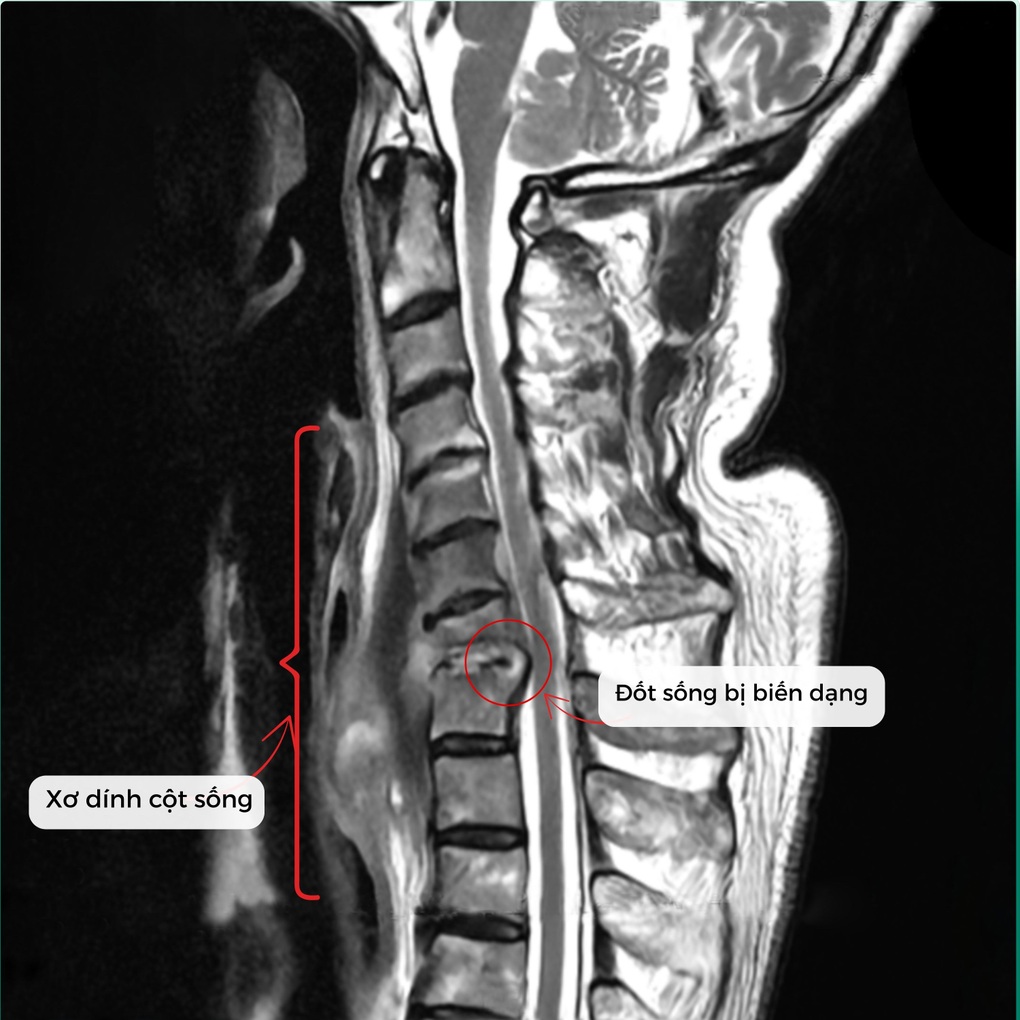

Tình trạng viêm, áp xe phá hủy thân đốt sống và đĩa đệm C7/T1, tạo dải xơ co kéo khiến cổ bệnh nhân luôn trong tư thế gập, không thể xoay, ngửa. Nếu không phẫu thuật sớm, người bệnh có nguy cơ liệt vận động rất cao.

Tình trạng xơ dính và đốt sống bị biến dạng trước phẫu thuật (Ảnh: BVCC).